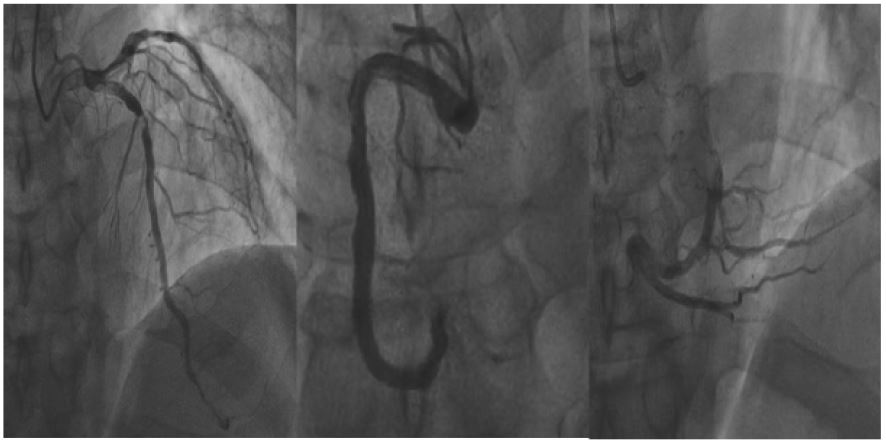

Figure 1: Findings of the patient at the first coronary angiography.

Cardiac enzymes: creatine kinase isoenzyme 4 ng/mL, myoglobin 220 ng/mL, troponin I 0.06 ng/mL. There were no obvious abnormalities in liver and kidney function, electrolytes and blood coagulation test. Urgent electrocardiogram showed sinus rhythm, Q wave formation in leads II, III, and aVF, and ST segment elevation of about 0.3 mV. The diagnosis was as follows: 1. coronary heart disease, acute ST-segment elevation myocardial infarction (inferior wall), cardiac function class I (Killip class) 2. Hypertension 3. Syphilis. Aspirin 0.3 g and ticagrelor 180 mg were given to the patient in bed. Emergency coronary angiography showed that there was no significant stenosis in the proximal segment of LM (left main artery), no significant stenosis in the proximal segment of LAD (Left Anterior Descending artery), thrombus stenosis in the middle segment of LAD was about 99%, and no significant stenosis in the distal segment. No obvious abnormality was found in LCX (left circumflex artery). The proximal segment stenosis of OM (Obtuse Marginal branch) was about 80%. RCA (right coronary artery) was thick with nonsmooth intima in the proximal and middle segments, and no significant stenosis was seen throughout (Figure 1). As the culprit vessel could not be located and the possibility of recanalization of RCA could not be excluded, urokinase 100000u and heparin 1000u were injected into the left and right coronary arteries respectively, and the operation was completed and the patient returned to the intensive care unit for hospitalization. The patient had no discomfort such as chest pain or chest tightness during and after the operation. Electrocardiogram was reexamined daily during admission, and pathological Q waves in leads II, III, and aVF were deepened, and ST segment gradually fell back to baseline level on the third day. Cardiac perfusion on the 5th day after admission showed acute ischemic cardiomyopathy changes in the inferior septal wall of the apical segment and the inferior wall of the left ventricle, and the inferior wall of the basal segment of the left ventricle, suggesting poor healing locally. Based on the results, the culprit vessel of this myocardial infarction was LAD. Reexamination of angiography on the 10th day after admission showed that the thrombus disappeared in the middle segment of LAD, the localized lesion was about 90%, and there was no significant change in LCX and RCA compared with before (Figure 2). Then a stent was implanted into the middle segment of LAD. The patient was discharged on the 12th day after admission.